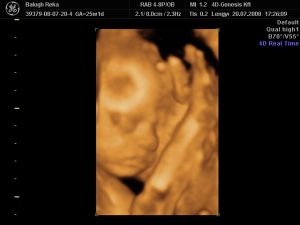

Na, most jöttem meg a 4d-ről.Annyira jó volt, nem hittem a szememnek.Láttam a kis nuniját, a szeméremajkait.

Már majdnem 1,5 kiló, mindene megvan, a kis fülei hihetetlenek voltak.És képzeljétek, mintha tudta volna, hogy produkálnia kell magát, mert ráncolta a homlokát, ásitott, ivott, mosolygott, és integetett. Mindene ok, tele volt épp a gyomra is meg a hólyagja is.Ja, és tök husi a pofija, olyan hörcsög...Nagyon nagyon édes.És mintha tudta volna, hogy lassan vége a vizsgálatnak, befordult a lepény mögé aludni.Ja, és tök hosszú a haja. Kis édes.

Szóval, ezt a 4d Genesist csak ajánlani tudom, nagyon profik, 30 perc az nem 25 és nagyon kedves a nő.